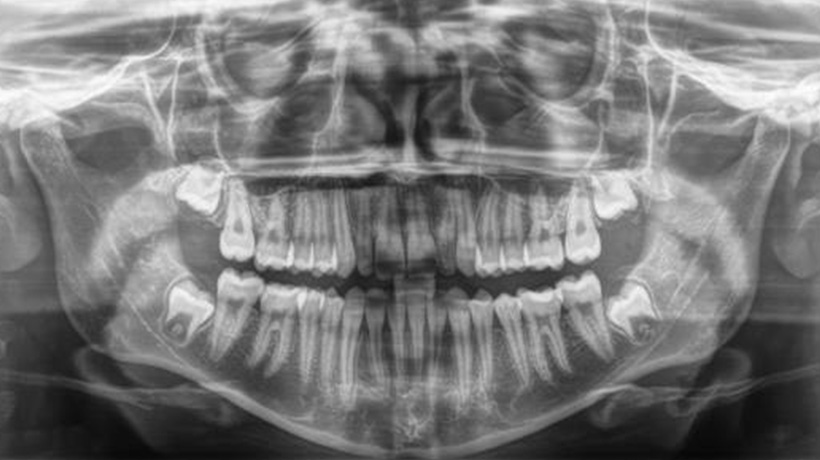

Ретинированные клыки

Создание места для прорезывания зуба